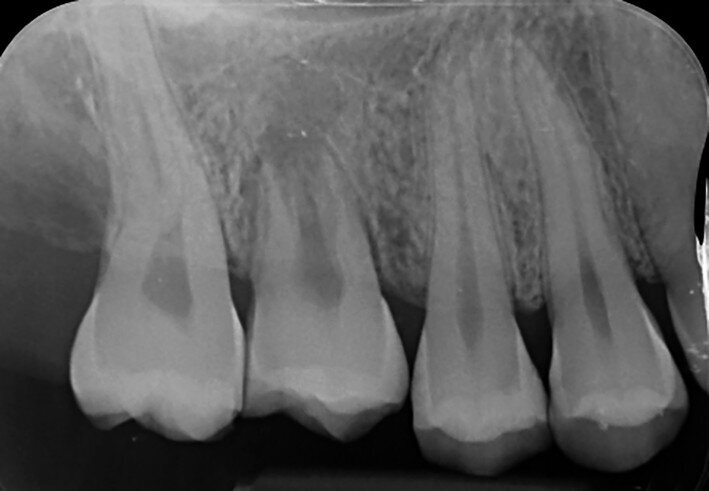

Fig. 16b: Radiograph at the one-year recall.

A right mandibular first molar of a 16-year-old female patient with heavy structural damage was extracted after explanation, informed consent and a mandibular block with 3 per cent mepivacaine. The receiving site was debrided, and the right mandibular third molar was atraumatically extracted, positioned in the alveolus and stabilised with sutures. An antibiotic (amoxicillin/clavulanic acid, 1 g, by mouth twice a day for five days) and a non-steroidal anti-inflammatory drug (ibuprofen, 600 mg, by mouth twice a day for five days) were prescribed, along with rinses with 0.2 per cent chlorhexidine. The sutures were removed after two weeks and the endodontic treatment was performed after two months. The tooth was still in full function after 11 years (Figs. 16a–d).